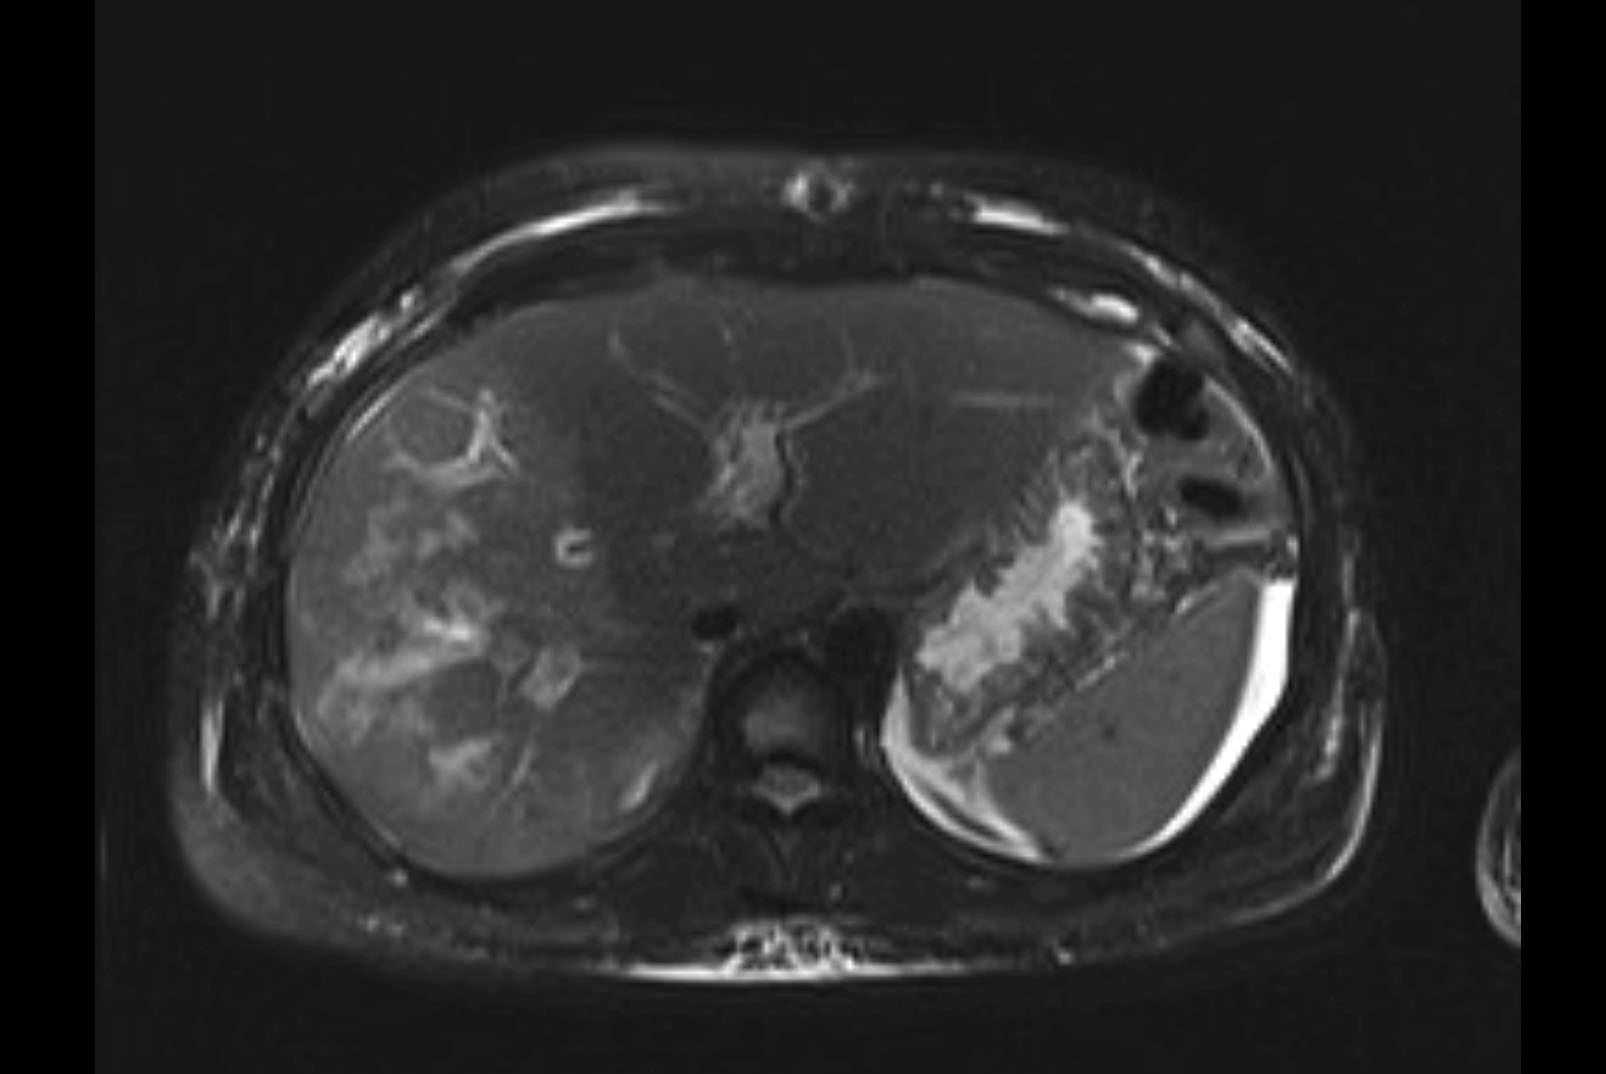

MRI T2